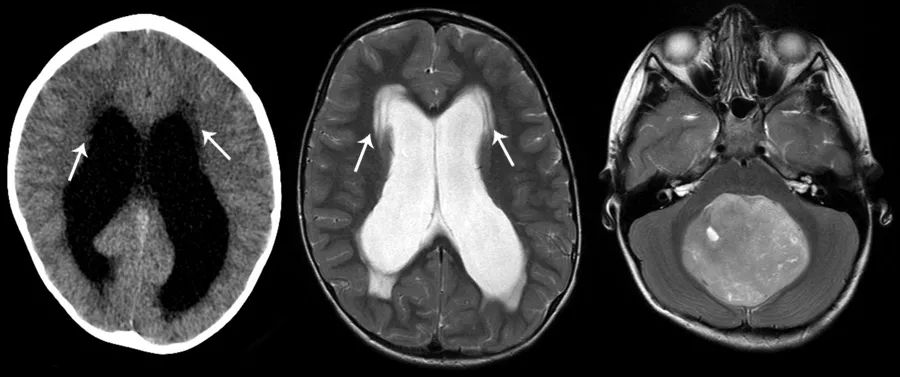

CT上,侧脑室周围可见脑室周围条片状低密度影,相邻脑沟消失,以及阻塞性脑积水的其他特征。MRI上的FLAIR序列对这种脑水肿的检测尤为敏感,侧脑室周围可见T2/FLAIR高信号的晕圈,边界通常较清。

图5 侧脑室周围可见条片状异常密度,CT上呈低密度,MRI的T2WI上呈高信号,边界较清(左、中)。本例患者的阻塞性脑积水由后颅窝占位导致(右)。